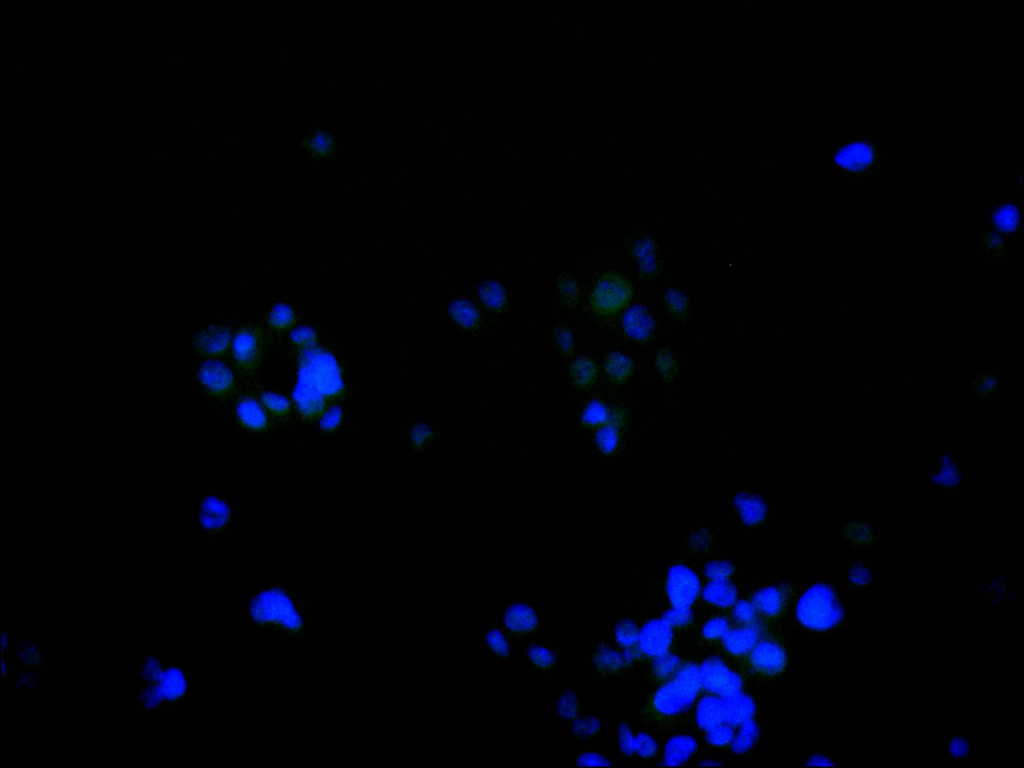

Immunofluorescence staining of HepG2 cell with CSB-RA546965A0HU at 1:50, counter-stained with DAPI. The cells were fixed in 4% formaldehyde, permeabilized using 0.2% Triton X-100 and blocked in 10% normal Goat Serum. The cells were then incubated with the antibody overnight at 4°C. The secondary antibody was Alexa Fluor 488-congugated AffiniPure Goat Anti-Rabbit IgG(H+L).